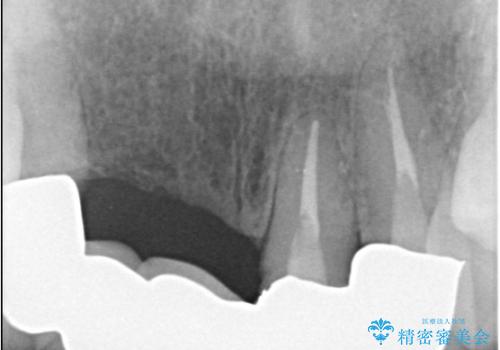

- 歯茎の大きな腫れを主訴に来院された患者様です。前歯5本にはブリッジが装着されていました。レントゲン検査より、右上3番に大きな根尖病巣が認められ、さらに左上1、2番の支台歯にも破折があったため、抜歯を行いました。その後、インプラントを3本埋入し、オールセラミッククラウンのブリッジで補綴しました。

術前のCT画像より、抜歯即時インプラントが可能と判断したため、抜歯と同時にインプラント埋入を行いました。術式にはセミルーナーフラップを用い、唇側の骨吸収を抑える目的でルートメンブレンテクニックを併用しました。